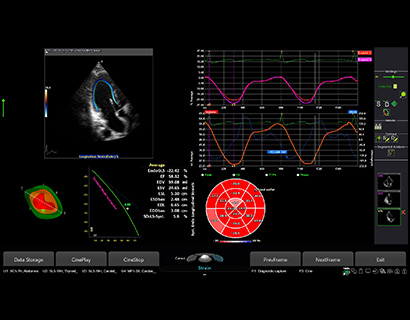

Phased array transducer (3-8MHz)

Application:

Abdomen, Cardiac, EM, Pediatric

MP1-5X(NEW)

X+ Crystal Signature™ phased array (1~5MHz)

Application:

Cardiac, TCD, EM, Abdomen, Pediatric

CW5.0

Pencil type transducer (5.0MHz)

Application:

Cardiac

CW2.0

Pencil type transducer (2.0MHz)

Application:

Cardiac